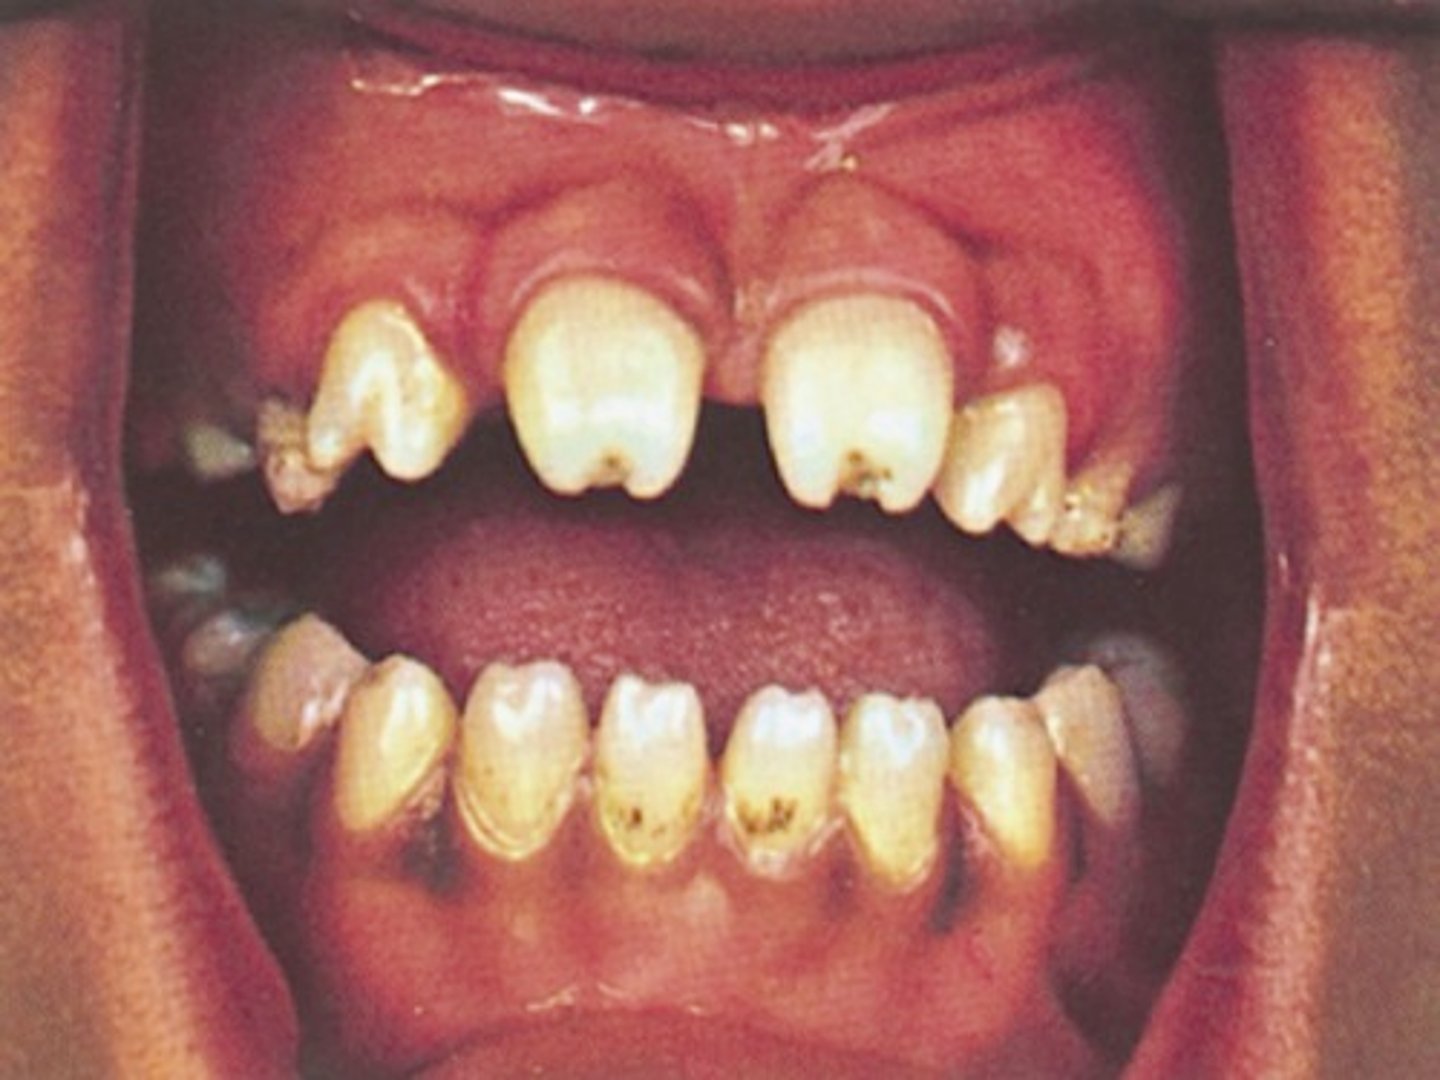

hutchinson's teeth

smaller teeth, widely spaced, notched surface

congenital syphilis

<p>smaller teeth, widely spaced, notched surface</p><p>congenital syphilis</p>